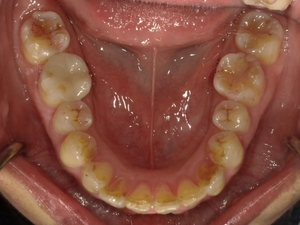

◯ご相談内容:歯がでたり引っ込んでいたりする◯矯正の種類:マウスピース型矯正「インビザラインGO」◯治療期間:17週間◯治療費用:44万円(税込)